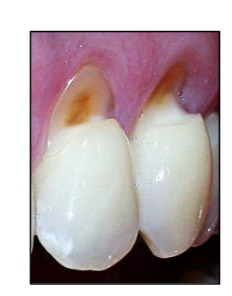

Observe a imagem a seguir.